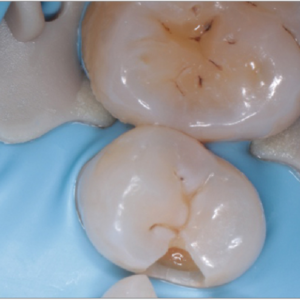

Para fijar el dique de muelas en casos de restauraciones de clase II con extensión distal.

Al utilizar el dique de muelas en la extensión distal, la pinza fija el dique de muelas y ayuda a dejar suficiente área de tratamiento